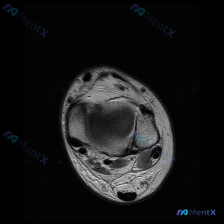

看到这张踝关节MRI,问题问有什么异常,很多人第一反应就是看到软组织积液,但其实背后藏着更关键的问题,我整理一下完整的分析思路给大家。 病例影像基础信息 这是一张踝关节MRI T2序列轴位影像,我们先把所有能看到的征象理清楚: 1. 骨骼结构:影像中心是距骨横截面,皮质骨低信号、骨髓中等信号,骨质轮...

看到这个踝关节MRI的病例,整理了完整的影像资料和分析思路,和大家分享讨论。 病例影像基础信息 这是踝关节MRI T2加权轴位图像,扫描层面为踝关节远端,可见距骨体及周围软组织结构,图像对比度满足观察要求,T2加权像液体呈高信号。 核心影像发现 1. 骨结构:距骨及周围骨性结构骨髓无异常高信号,骨皮...

刚看到这份踝关节MRI读片需求,整理了完整的观察和分析思路分享给大家。 病例基本影像信息 本次读片基于踝关节MRI-T2序列轴位图像,扫描层面为踝关节远端轴位,可清晰辨认胫骨、腓骨、距骨以及后方跟腱等正常解剖结构。T2序列对液体和水肿敏感,正常肌腱韧带应为低信号(黑色),液体/水肿为高信号(白色)。...

刚整理完一份踝关节MRI的读片分析,关于软组织积液的鉴别思路挺典型,分享给大家一起讨论。 病例影像基本信息 这是一份踝关节MRI T2序列轴位影像,扫描层面为距骨体水平,显示踝关节及周围软组织结构: 1. 骨骼表现:距骨及周围骨性结构骨皮质完整,骨髓信号无局灶异常高信号,排除明显骨挫伤、骨折或骨髓水...

刚看到这张踝关节T2轴位MRI,我整理一下影像表现和分析思路,跟大家讨论一下。 病例影像基本信息 这是踝关节轴位T2加权MRI,液体呈高信号(亮白色),骨皮质、肌腱韧带呈低信号(黑色)。 先看基础结构: - 骨性结构:胫骨、腓骨、距骨截面可见,骨髓信号均匀,没有明显骨质破坏或异常骨髓水肿 - 肌腱结...

最近看到一份踝关节MRI的影像分析,整理了整个诊断思路分享给大家,一起讨论下。 病例影像基本信息 这是踝关节轴位T2加权MRI扫描,核心发现整理如下: 1. 骨骼结构:胫骨、腓骨、距骨骨皮质完整,没有骨折线,骨髓信号均匀,无明显弥漫性骨髓水肿 2. 肌腱韧带:内外侧肌腱、跟腱走行正常,信号均匀,无腱...

今天整理了一份踝关节MRI的读片分析,核心问题是影像发现「软组织积液」该怎么判断,分享出来大家一起讨论。 病例影像基础信息 这是一份踝关节轴位T2加权MRI(T2WI)的读片报告,核心信息整理如下: 1. 骨骼结构:胫骨远端、距骨骨髓信号正常,无骨髓水肿、骨质破坏,皮质完整,未见骨折线 2. 关节结...